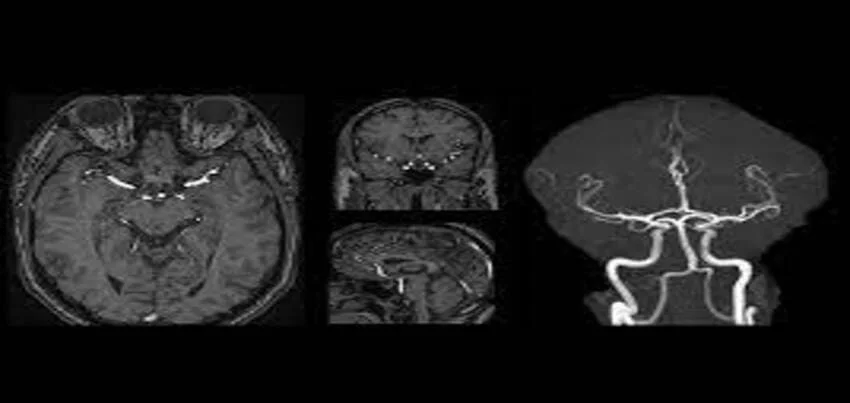

MRI Angiography Of Brain Or MRA Of Brain

Magnetic Resonance Angiography (MRA) of the brain is a non-invasive medical imaging test that uses a powerful magnetic field, radio waves, and a computer to create detailed images of the blood vessels in the brain. It provides valuable information about the structure and function of the blood vessels, helping physicians diagnose and treat a variety of conditions.

MRA of brain

Interpreting the results of an MRA of the brain requires specialized training and expertise. The images produced by the MRA machine are highly detailed and may reveal subtle changes in the blood vessels of the brain. A radiologist or neurologist typically reviews the images and provides a report to the referring physician.

The results of an MRA of the brain may indicate the presence of aneurysms, AVMs, or other vascular abnormalities that require further testing or treatment. The images may also reveal evidence of stroke or other cerebrovascular disorders, such as narrowing or blockage of the blood vessels in the brain.